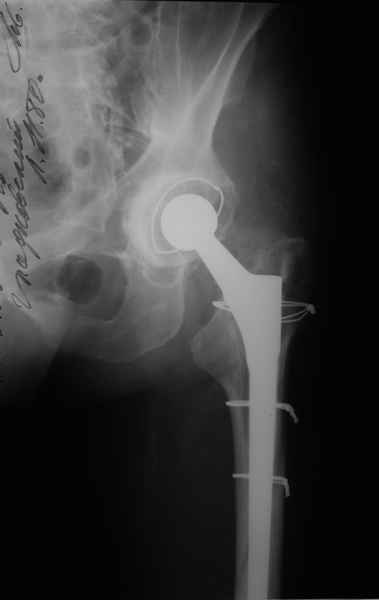

2. Применение ножки дистальной фиксации, мы отдаем предпочтение ножке Вагнера с фиксацией проксимального отдела на ножке. Более травматичное вмешательство, но при стабильной фиксации ножки реабилитация идет в обычном режиме.

Хочется показать два подобных случая, П-ка З. 72 лет и п-т Г. 80 лет. Сразу принимаю замечание, что это были ножки цементной фиксации, просто под руками не было бесцементника.